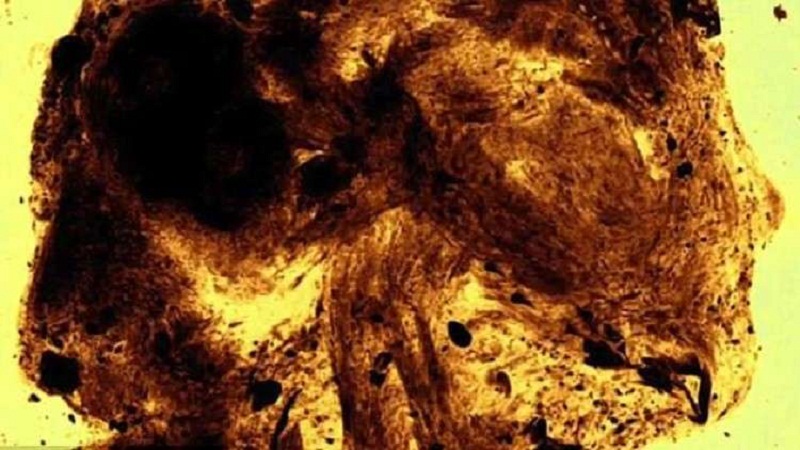

وأظهر تحليل جديد للمومياء التي يبلغ عمرها 2100 عام، أنها لم تكن طائرا بل جنينا بشريا ميتا.

ويقول الخبراء إن الجنين مات في غضون 23-28 أسبوعا فقط من الحمل بجمجمة شديدة التشوه، ما دفع العائلة إلى إجراء عملية تحنيط نادرة ومذهلة.

وتم التعريف عن المومياء بشكل خاطئ في متحف Maidstone البريطاني، باسم “صقر العصر البطلمي المحنط”، إلى أن كشف التصوير المقطعي في عام 2016 أنها إنسان، الأمر الذي فاجئ العديد من الخبراء. ولكن الأشعة المقطعية كشفت القليل من التفاصيل عن الجسم الصغير.

ولمعرفة المزيد، اتخذ فريق نيلسون خطوات جديدة في التحقيق من خلال العمل مع المتحف وNikon Metrology، حيث أجروا فحصا دقيقا وحققوا ما يمكن أن يكون المسح الضوئي الأفضل على الإطلاق لمومياء جنينية، وفقا لنيلسون.

وكشفت الدراسة بعد “الافتراض العلمي” عن وجود تشوهات صادمة مميزة لظاهرة نادرة تسمى “انعدام الدماغ”. وقال نيلسون: “الجزء الأكبر من الجمجمة لم يتشكل. كما لم تُغلق أقواس فقرات العمود الفقري، كما تتواجد عظام الأذن في مؤخرة الرأس”.